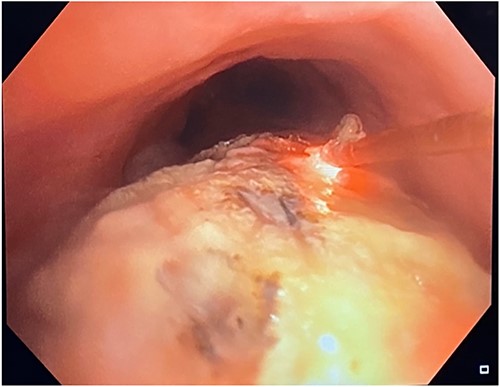

This was the first clear evidence of esophagotracheal communication. Laser debridement was successfully performed again in November 2022, leaving only a small portion where the stent eroded the trachea. On post-bronchoscopy Day 3, the patient reported significant improvements in breathing and energy. Over 6 months, she underwent laser debulking of the tracheal mass twice to manage tumor ingrowth (January and April 2023). Debridement was performed each time using a neodymium-yttrium-aluminum-garnet laser (Fig. 4). Between 380 and 560 joules were delivered to cauterize and debulk the invading tumor. The patient continues to be followed for palliative tumor debulking for ongoing symptom management.

Bronchoscopic view of the endobronchial obstruction. Invasion of the esophageal malignancy can be seen, as well as erosion of the esophageal stent into the lumen of the trachea.